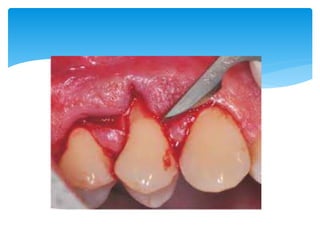

Colgajo desplazado hacia apical

Crear acceso Para las cirugia osea

Tratamientos de bolsas infraoseas

Crear acceso Para el alisado radicular

Objetivo

 Es empleadoPara la eliminacion de bolsas y ensanchamiento de la encia insertada, dependiendo del objetivo se tratara de un colgajo de espesor completo o espesor parcial.  https://youtu.be/Jfy5bqgn3FU Colgajo desplazado hacia apical

Crear acceso Paralas cirugia osea Tratamientos de bolsas infraoseas Crear acceso Para el alisado radicular Objetivo